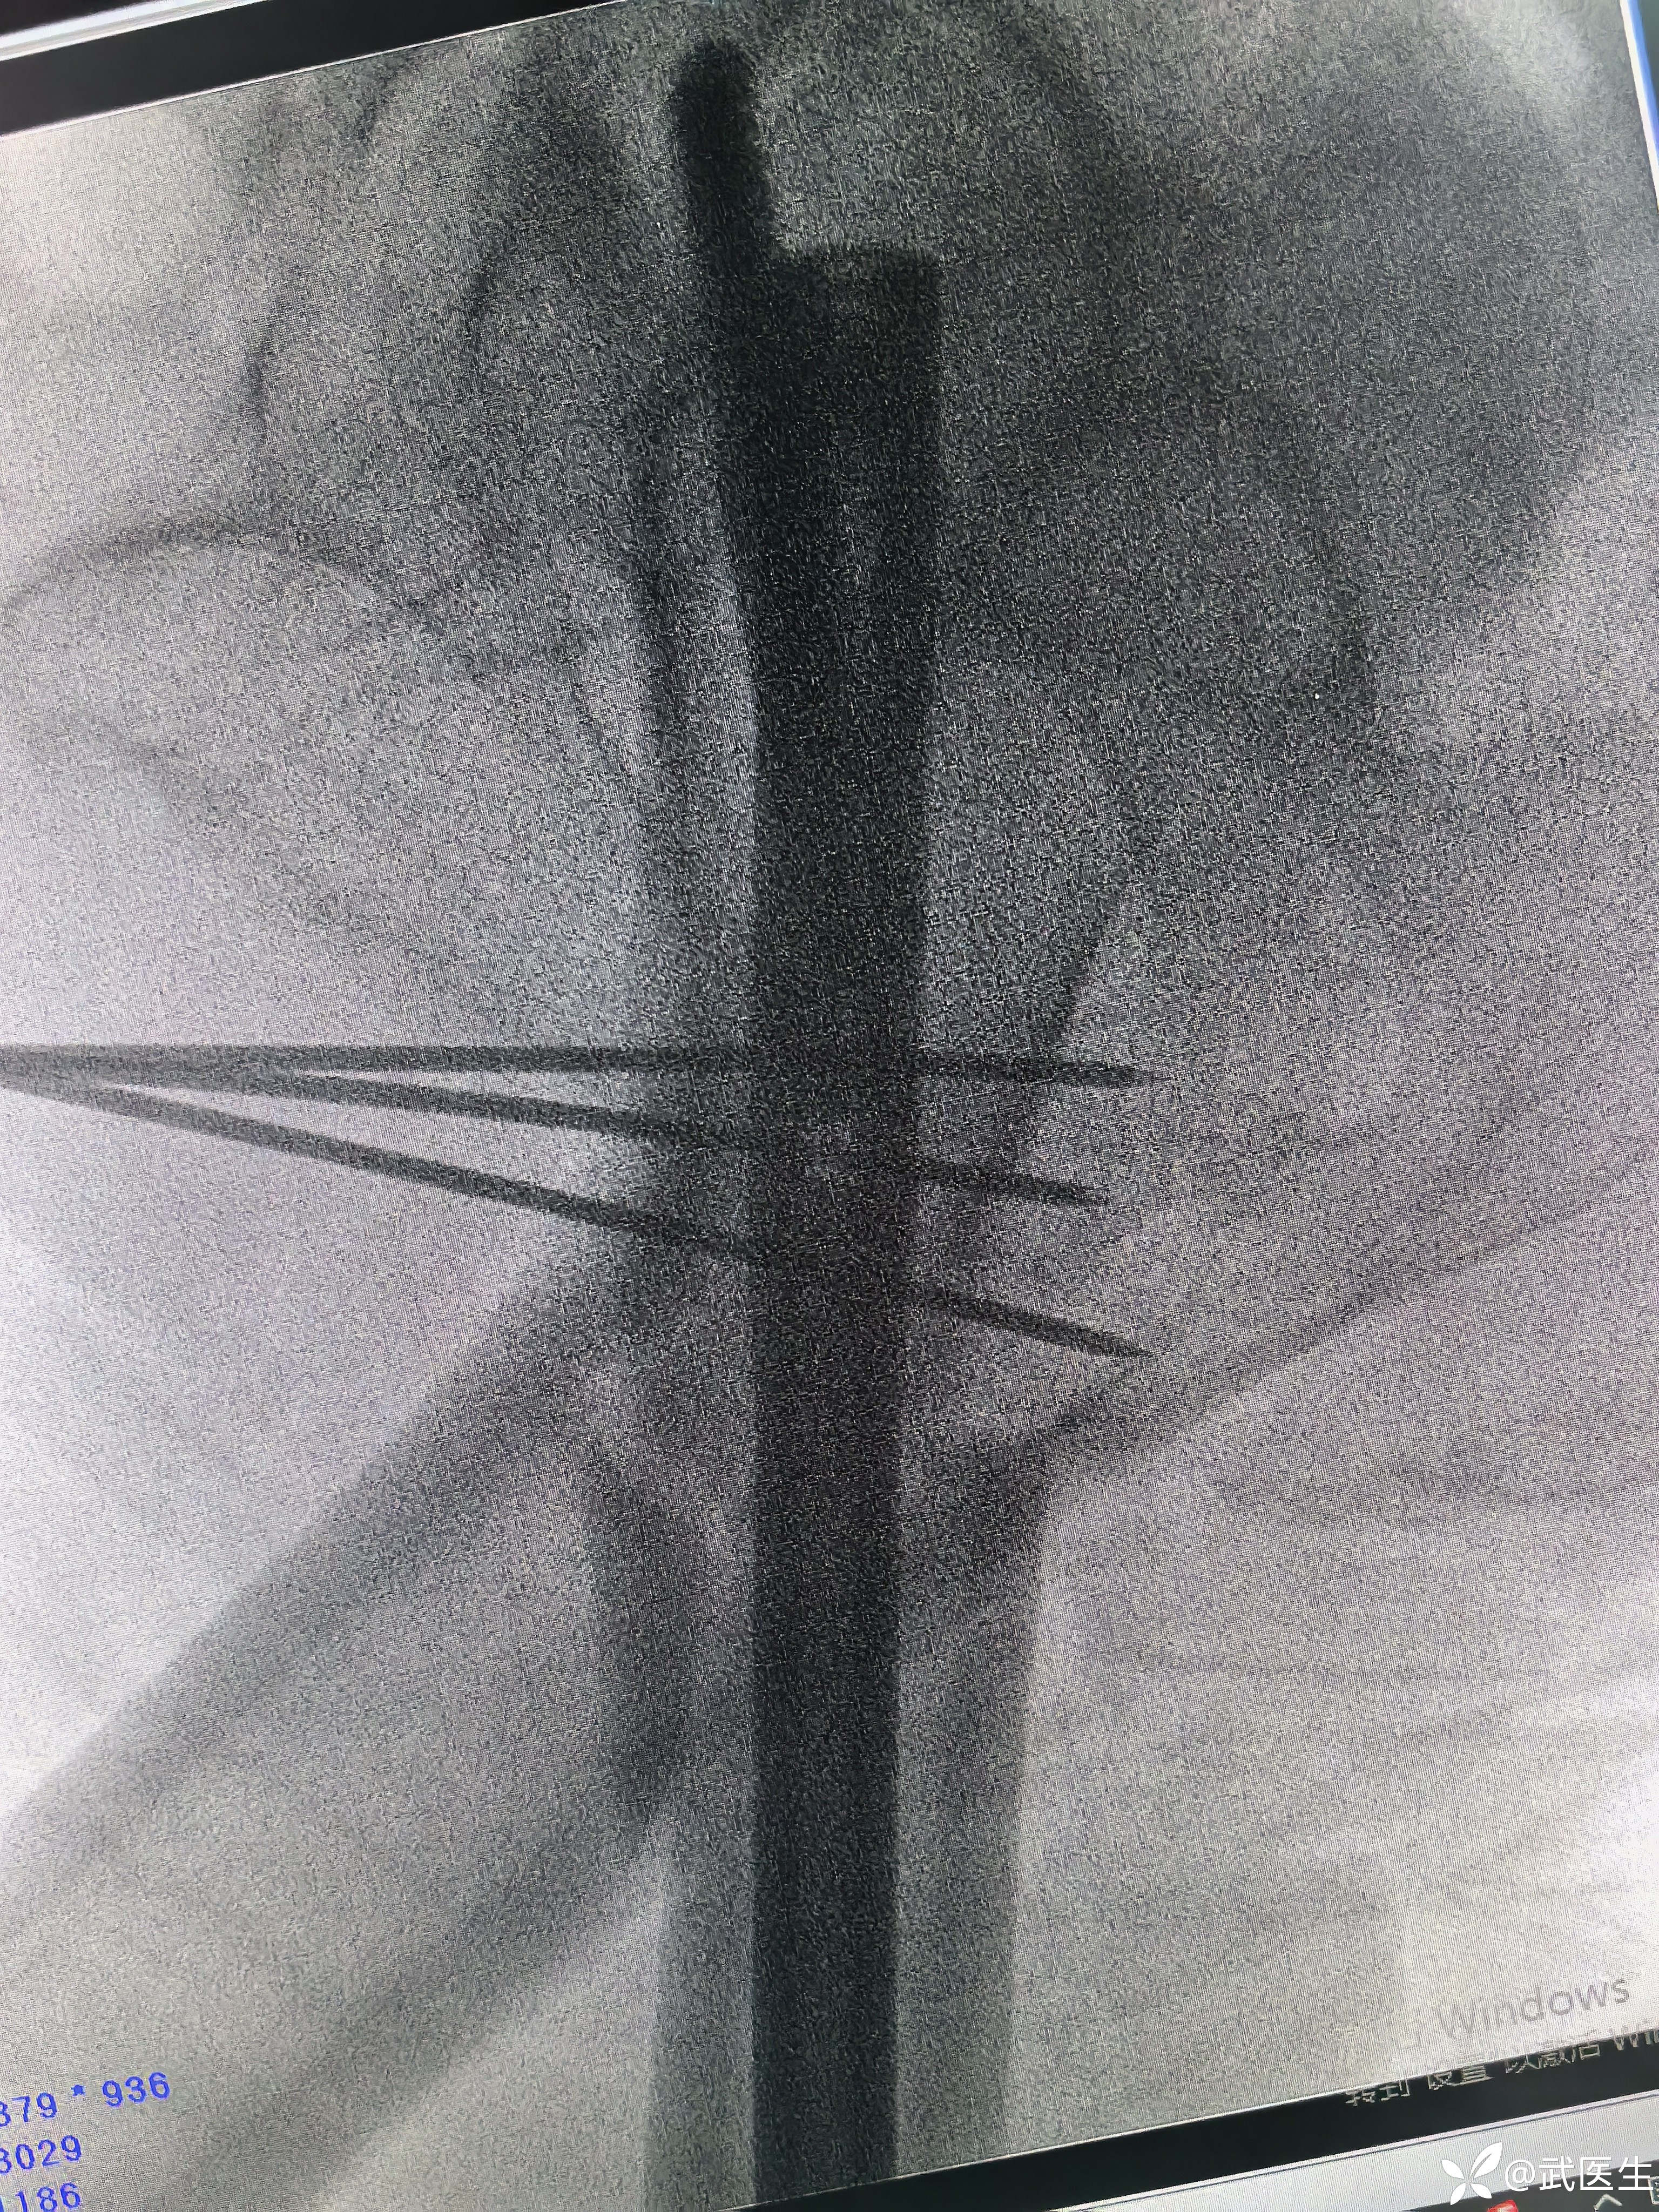

捶足底,纵向挤压

间隙缩小

侧位前方出现蝶形骨块